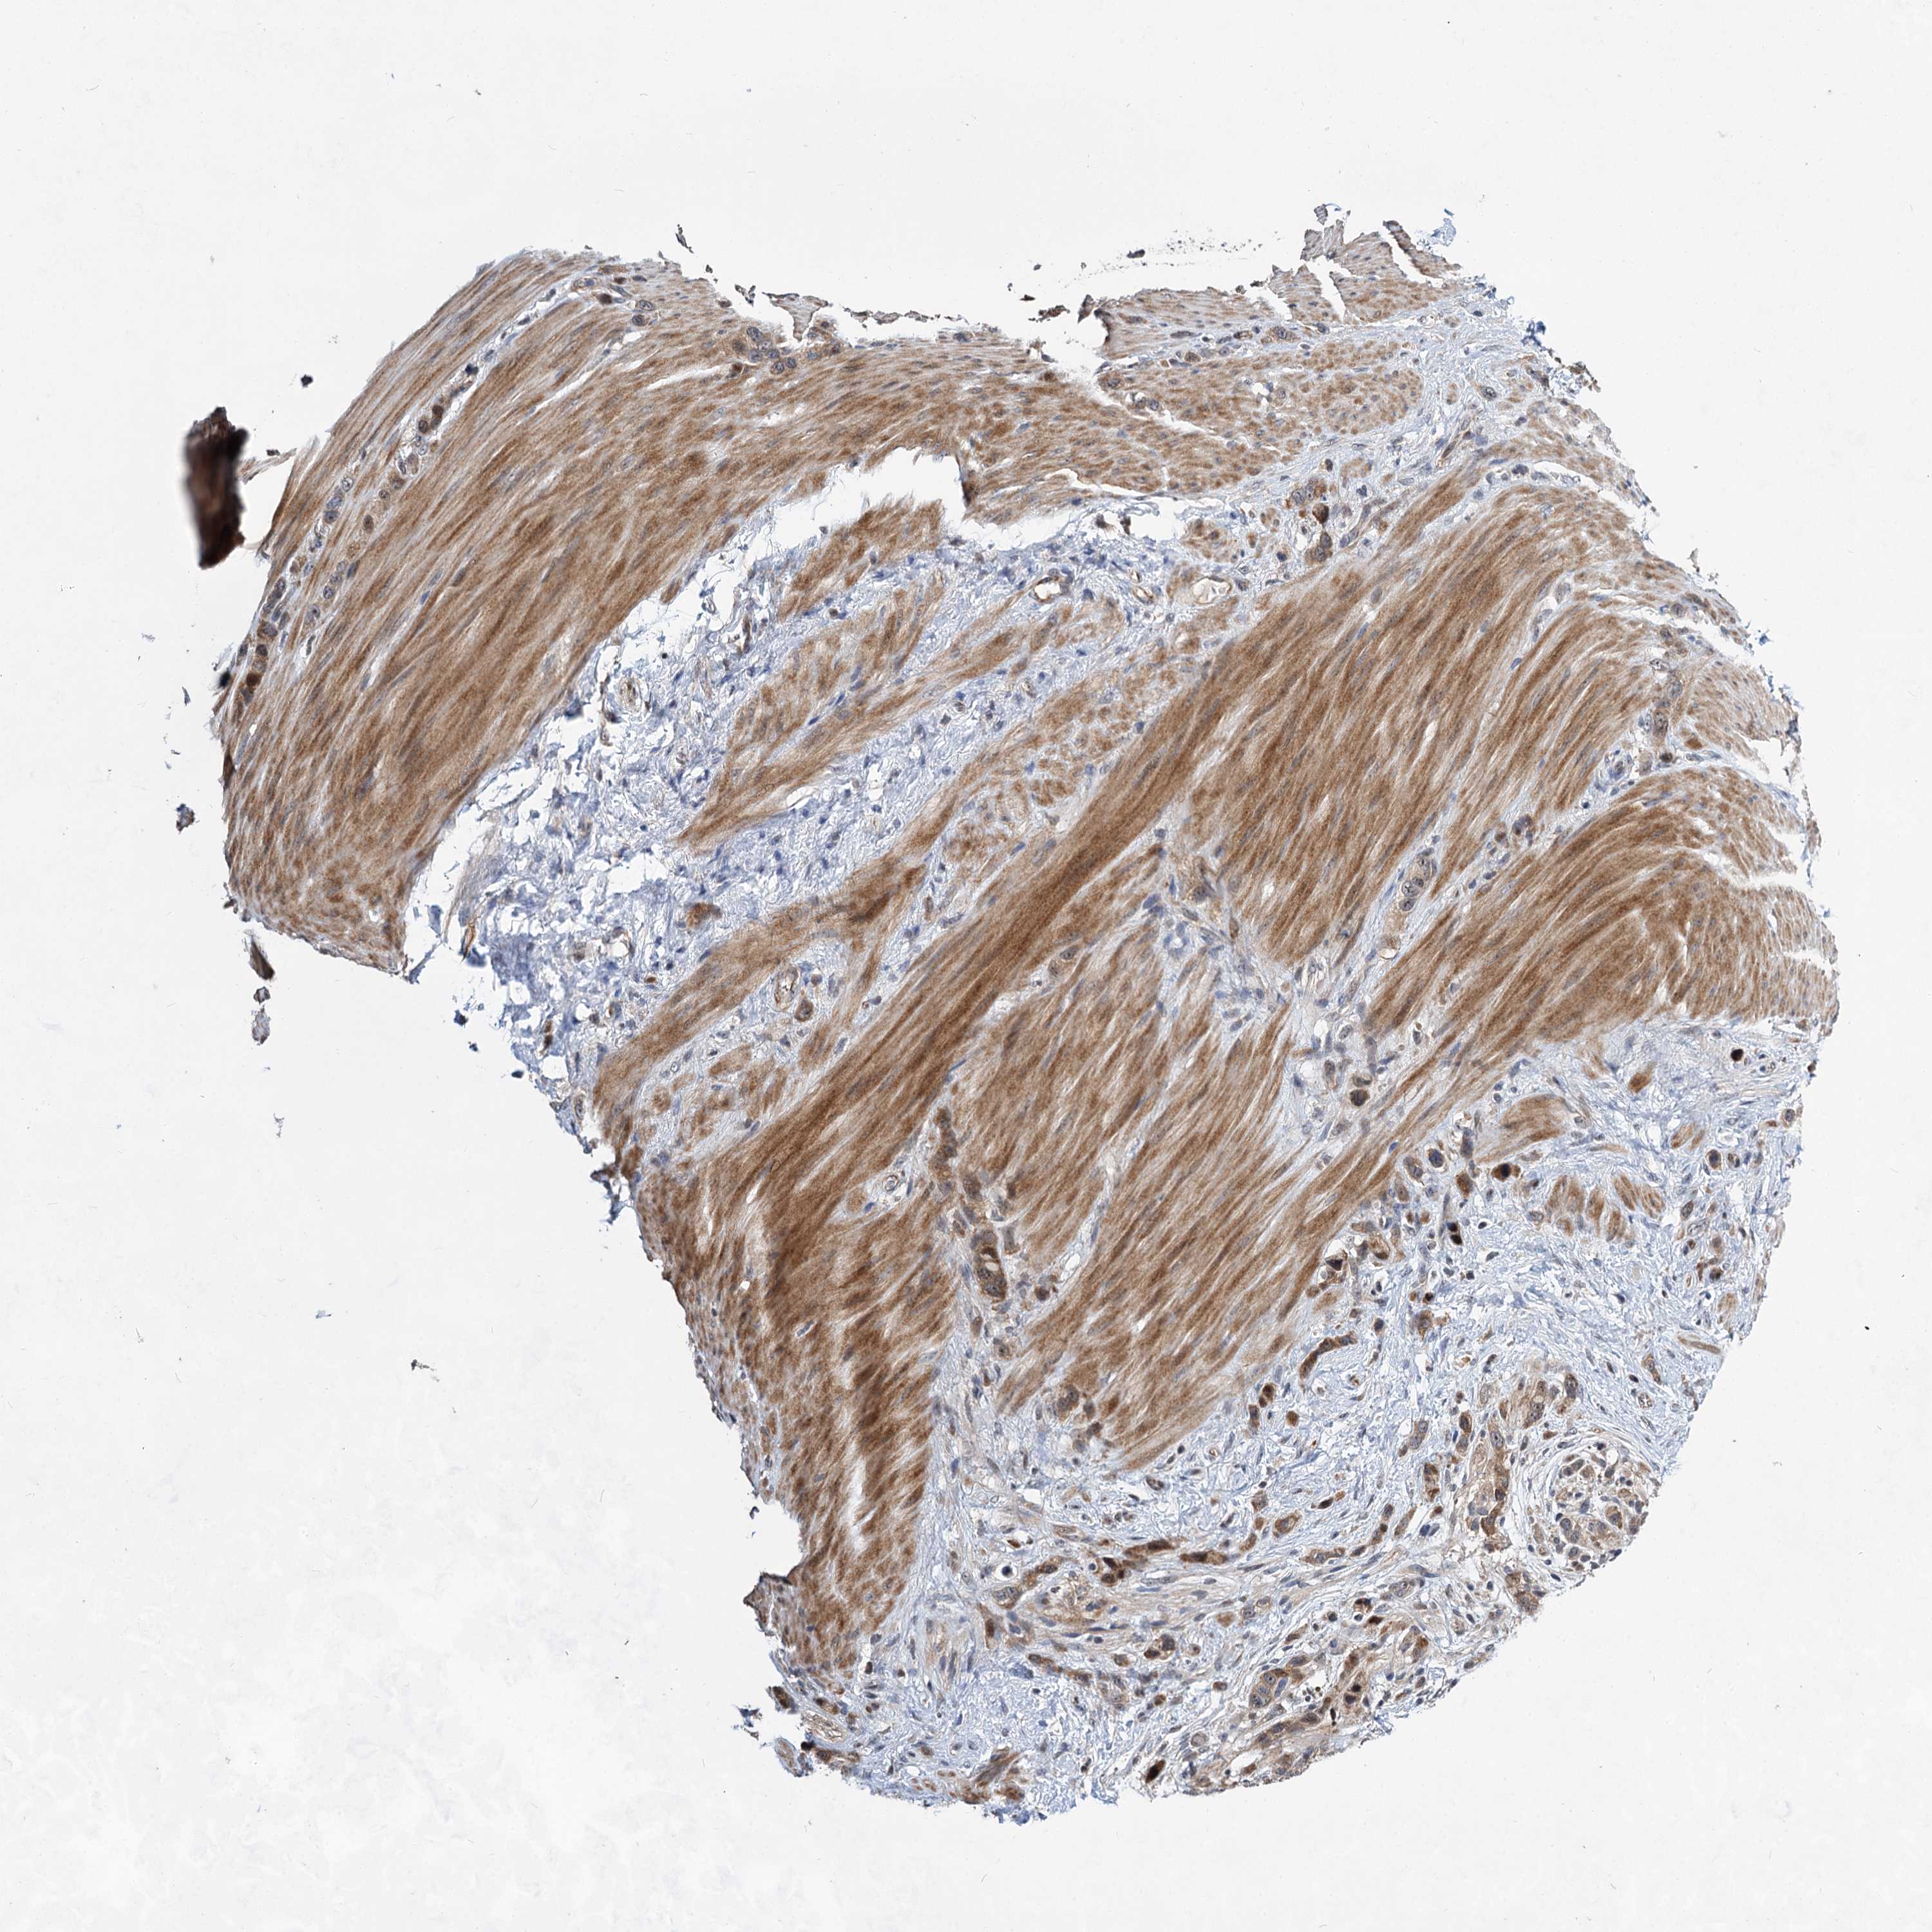

STOMACH CANCER - Protein expressioni

A mouse-over function shows sample information and annotation data. Click on an image to view it in a full screen mode. Samples can be filtered based on level of antibody staining by selecting one or several of the following categories: high, medium, low and not detected. The assay and annotation is described here.

Antibody stainingi

Antibody staining in the annotated cell types in the current human tissue is reported as not detected, low, medium, or high, based on conventional immunohistochemistry profiling in selected tissues. This score is based on the combination of the staining intensity and fraction of stained cells.

Each image is clickable and will lead to virtual microscopy that enables deeper exploration of all samples and also displays staining intensity scores, fraction scores and subcellular localization as well as patient and tissue information for each sample.

Antibody HPA037773

Staining

High

Medium

Low

Not detected

Intensity

Strong

Moderate

Weak

Negative

Quantity

>75%

75%-25%

<25%

None

Location

Nuclear

Cytoplasmic/membranous

Cytoplasmic/membranous,nuclear

Adenocarcinoma, NOS